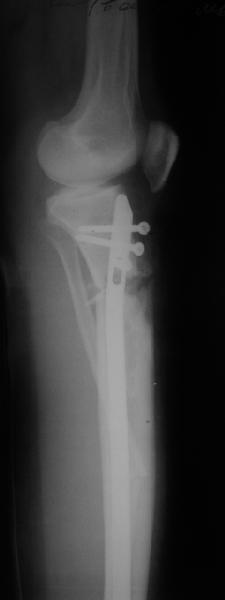

Наконец-то оперировали эту пациентку. Биопсию сделали - опухолевого ничего нет. Пока все участвовавшие в обследовании смежные специалисты и ортопеды сошлись, что это молокальная монооссальная фиброзная дисплазия.

20 марта наложили аппарат, сделали чрескожную остеотомию. К 3 апреля все докрутили. Сегодня заштифтовали. Начальные и итоговые снимки в приложении. Рекурвацию можно было еще немного больше устранить, и чуть кзади сместить диафиз. Но вроде и так ничего выглядит, по сравнению с тем, что было. Комментарии приветствуются.